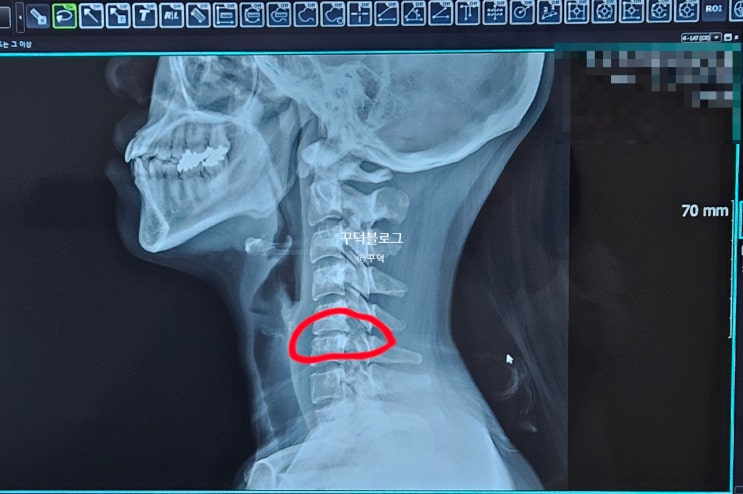

목디스크 검사, MRI촬영 꼭 필요한가? 비싸다고 소문난 MRI비용은?

한의원에서 목디스크 증상이 맞다고 진단을 받은 후의 이야기입니다. 목디스크 검사 때 비싼 MRI촬영 필...